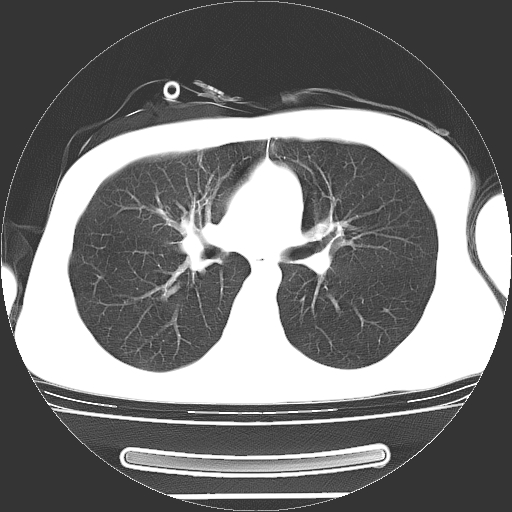

标题: CT19767:男,20岁,右侧气胸行闭式引流术后五天CT检查。 [打印本页]

男,20岁,右侧气胸行闭式引流术后五天ct检查看肺内是否有肺大泡,纵隔窗未见异常,未上传。

1)右侧胸腔闭式引流术后导管留置。2)右肺未见肺大泡。

未见肺大泡,还有微量气体。